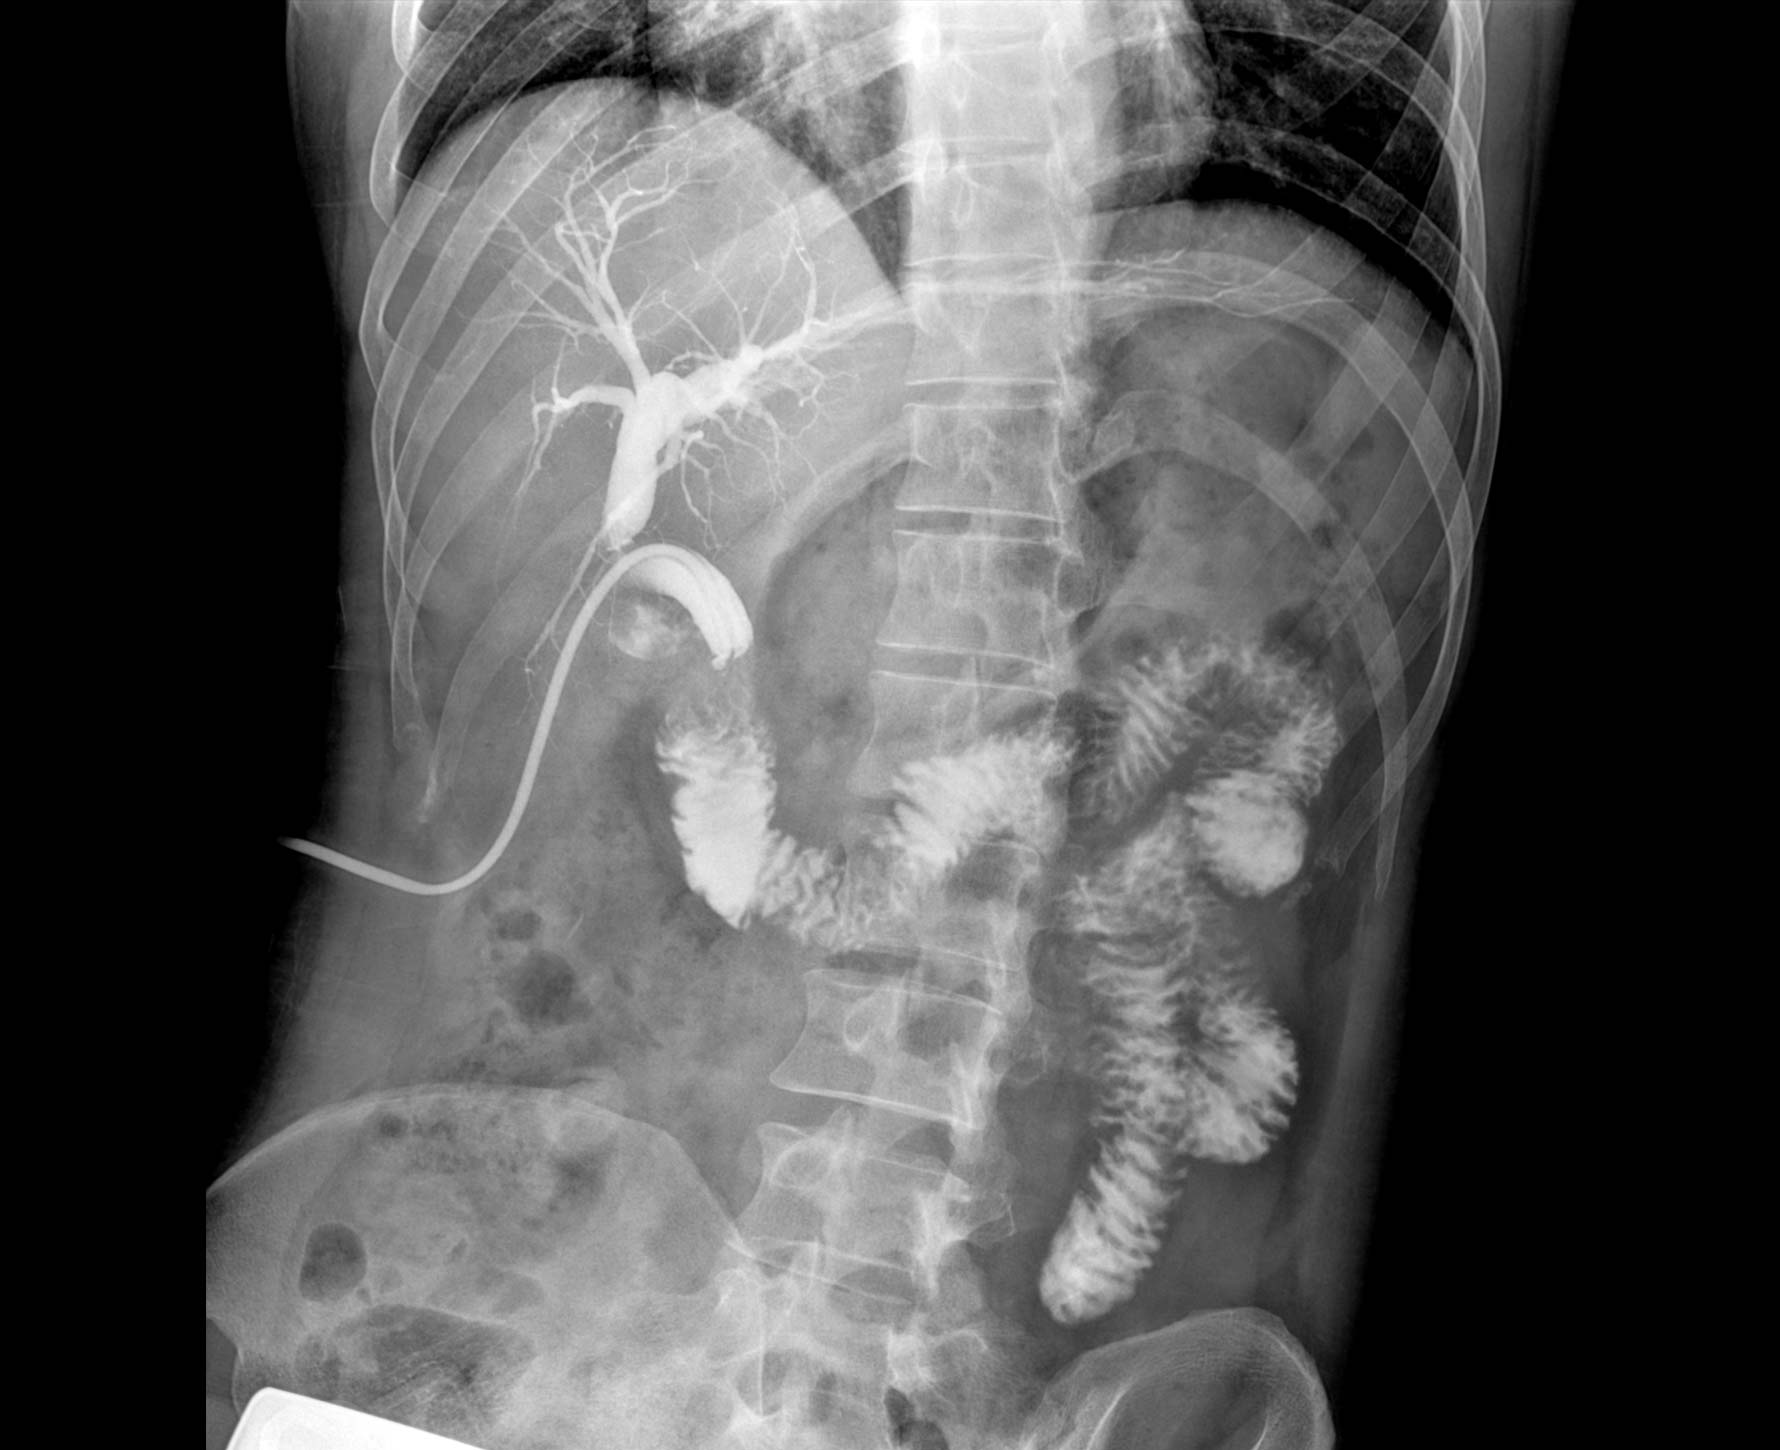

• 造影

适用于各种普通

及特殊胃肠造影检查

对胃肠造影检查影像实时保存,多次回放以便确定病灶部位,患者确诊好帮手,减少漏诊。

临床图像